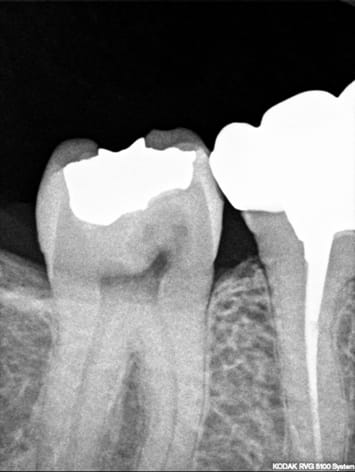

Mon premier pink spot (je suis content y a pas que des conneries ds les confs) mais j ai un doute :

La résorption interne à presque effondré la face vestibulaire de cette 47 (aucun souvenir de trauma), bref :

Quelle est l’etiologie de cette RI ??

Quel traitement : un TR et une couronne c est bon ou y a risque de fragilité ???

Tous les éléments sont présents pour effectivement suspecter une resorption interne.

2- : on considere que l'etiologie est une inflamation chornique de la pulpe et dans ce cas, seule la pulpectomie va permettre de stopper le phenomene. A partir du moment ou on retire la pulpe, on stoppe le phenomene; ce qui peut etre indiqué dans ce cas precis.

la difficulté technique est que ce tissu inflammatoire est tres hemorragique. Le traitement doit idéalement se faire en deux temps :

1- ouvrir la dent sous anesthésie, cureter tout ce qu'il est possible d'enlever; mettre dans la chmabre un hydrocyde de calium pur bien compacte ; l'interet de cette temportisation est que ce produit va bruler tous les residus de parenchyme. Le materiau est laissé en place pendant 15j-3semaines.

2- en rouvrant a la deuxieme seance, la cavité est nickelle, le tissu resorbé peut etre retiré facilement avec une fraise, et le traitement endodontique réalisé

en fonction de la hauteur de la communication avec le parodonte, une ginigvectime permettra probablement de repositionner la limite au dessus du niveau gingival.